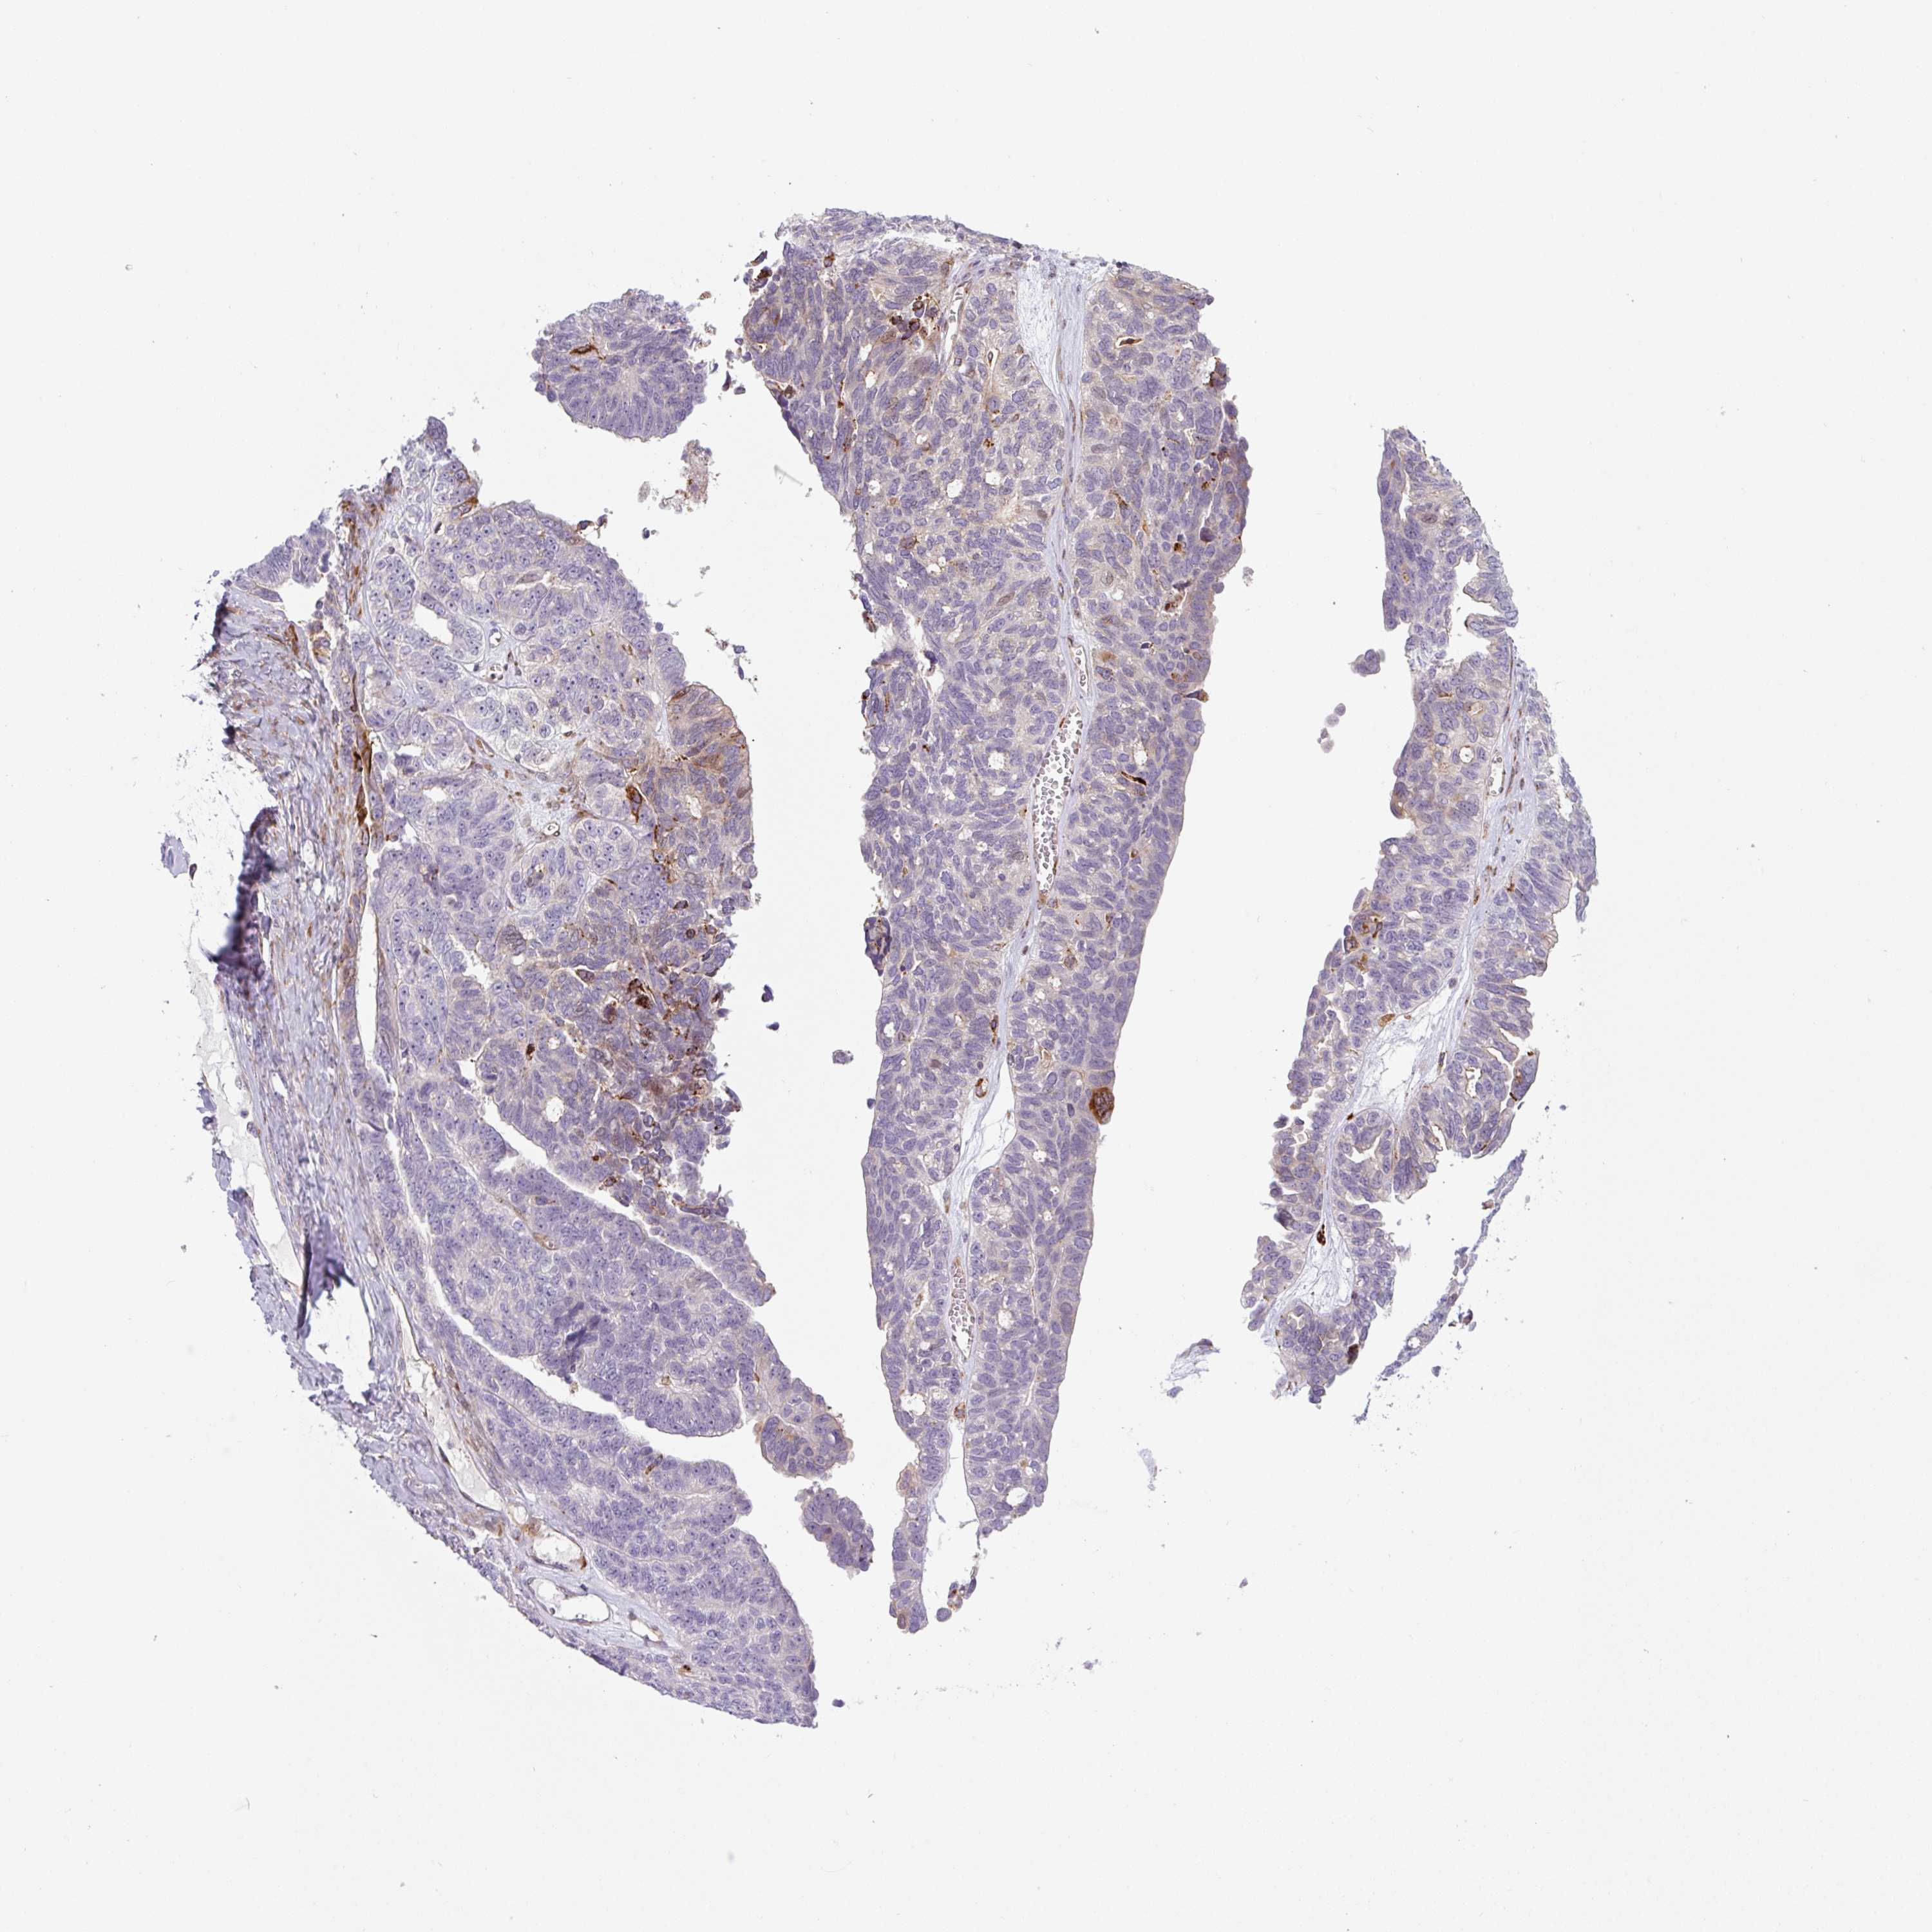

OVARIAN CANCER - Protein expressioni

A mouse-over function shows sample information and annotation data. Click on an image to view it in a full screen mode. Samples can be filtered based on level of antibody staining by selecting one or several of the following categories: high, medium, low and not detected. The assay and annotation is described here.

Note that samples used for immunohistochemistry by the Human Protein Atlas do not correspond to samples in the TCGA dataset.

Antibody stainingi

Antibody staining in the annotated cell types in the current human tissue is reported as not detected, low, medium, or high, based on conventional immunohistochemistry profiling in selected tissues. This score is based on the combination of the staining intensity and fraction of stained cells.

Each image is clickable and will lead to virtual microscopy that enables deeper exploration of all samples and also displays staining intensity scores, fraction scores and subcellular localization as well as patient and tissue information for each sample.

Antibody HPA054579

Staining

High

Medium

Low

Not detected

Intensity

Strong

Moderate

Weak

Negative

Quantity

>75%

75%-25%

<25%

None

Location

Nuclear

Cytoplasmic/membranous

Cytoplasmic/membranous,nuclear

Cystadenocarcinoma, serous, NOS

Carcinoma, endometroid

Cystadenocarcinoma, mucinous, NOS

Carcinoma, NOS